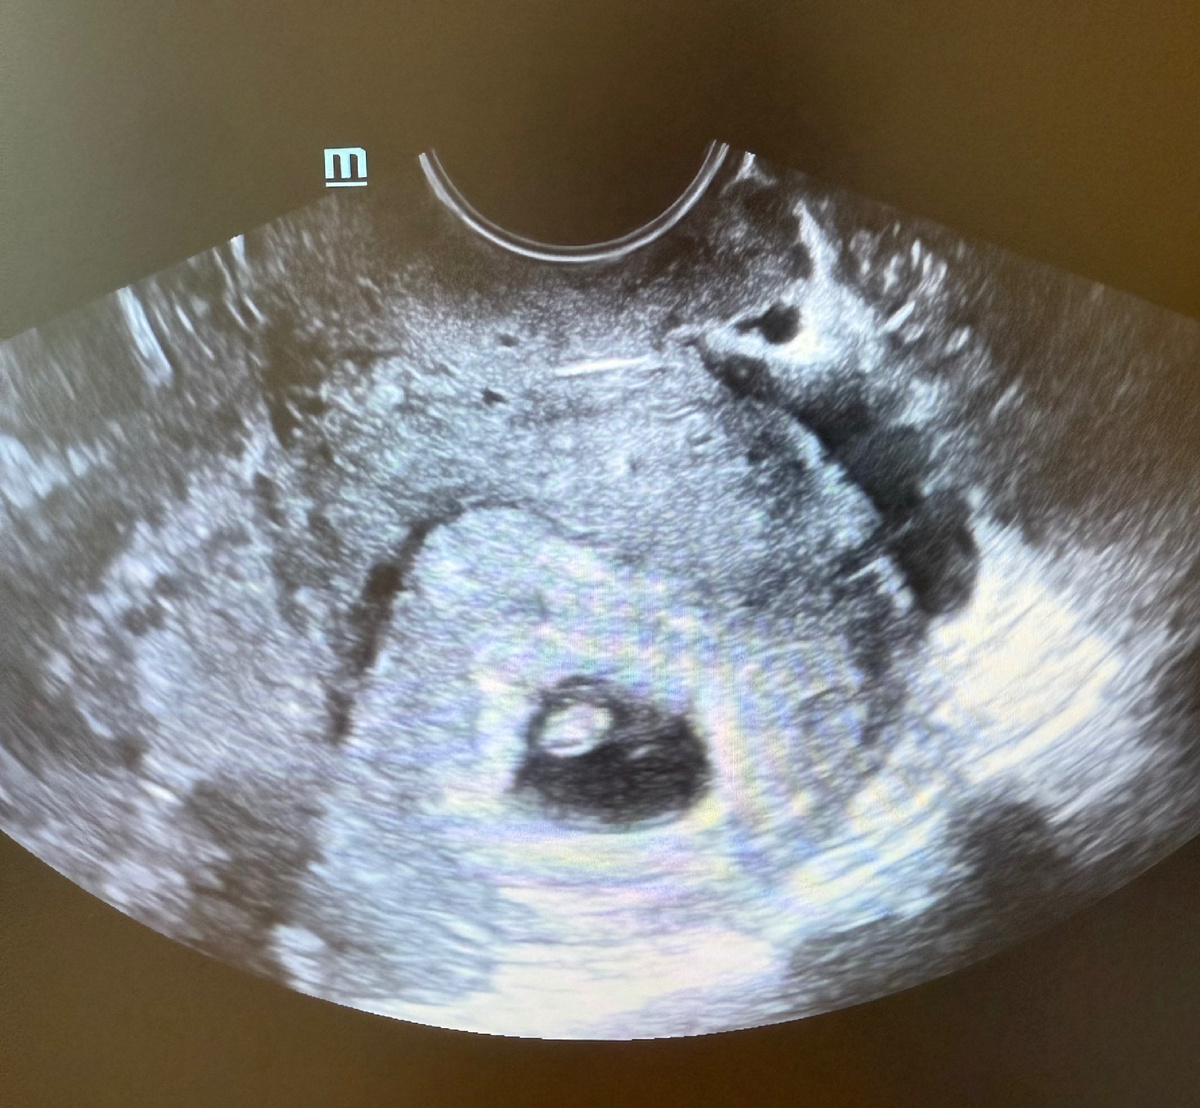

-Понятно. Проходите на кушетку, сделаем УЗИ.

На УЗИ обнаруживаем беременность 5 недель.